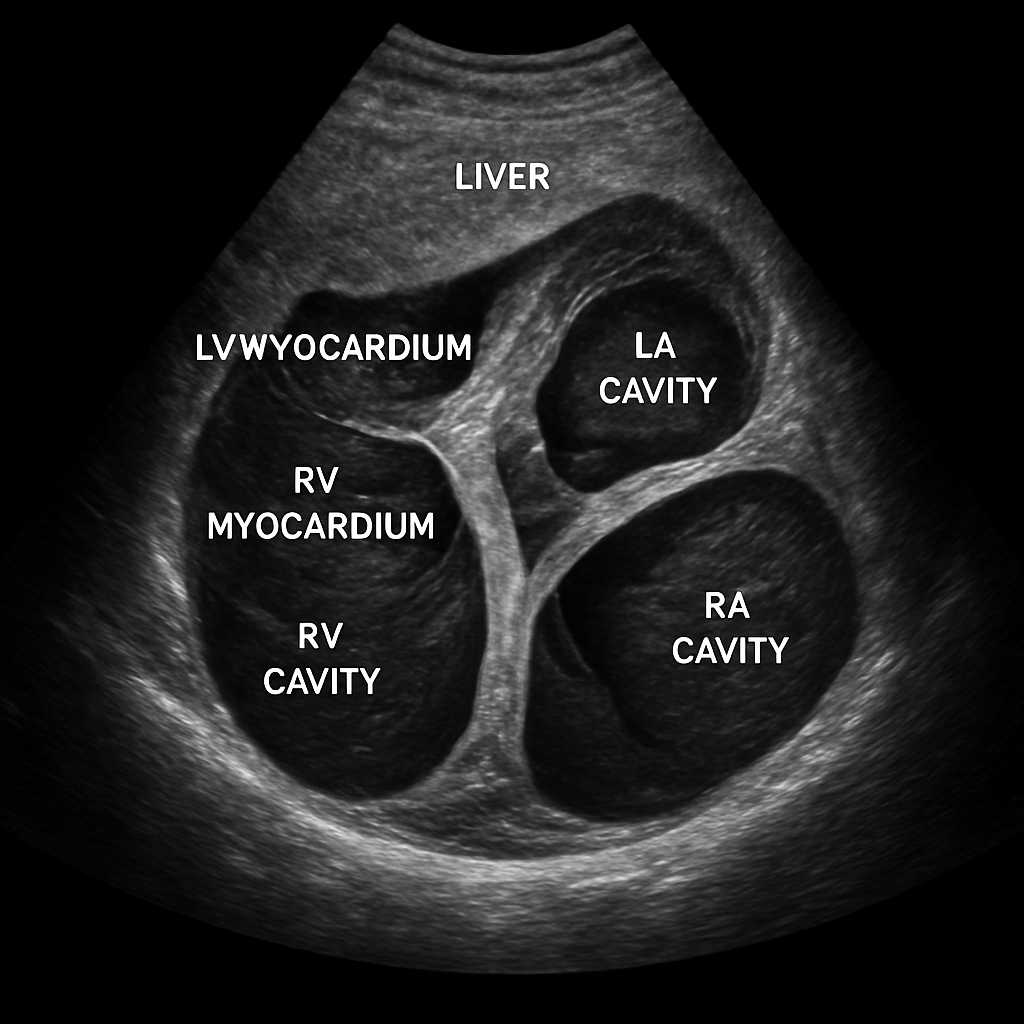

Echo — Subcostal Four-Chamber

Transthoracic echocardiogram subcostal four-chamber view showing all chambers from a subxiphoid approach. Liver visible at top of image.

ULTRASOUND AI Generated 2026-03-16

Subcostal Four Chamber

2D B-mode TTE, subcostal 4C view. Liver at near field, then heart with all four chambers.